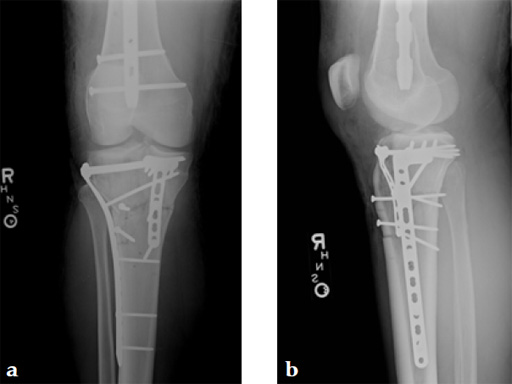

A 36-year-old man sustained a motorcycle injury: right femoral shaft fracture and right hyperextension bicondylar tibial plateau variant (Fig 1, Fig 2).

Staged management with initial rodding of femur and placement of spanning knee external fixator with closed manipulative reduction of tibial plateau (Fig 3).